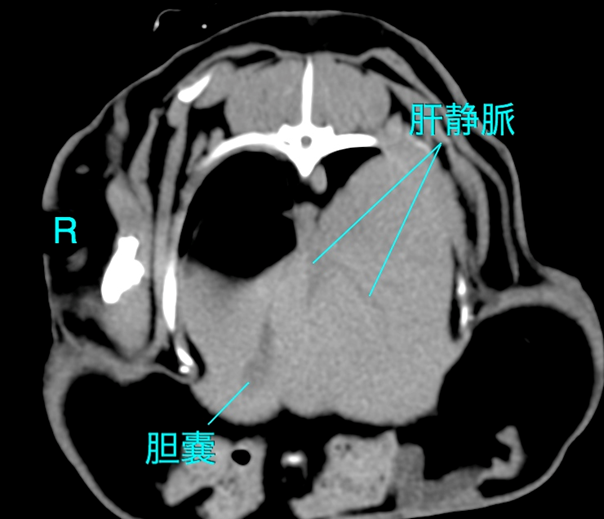

CT検査

CT検査は、X線吸収値(CT値)を用いて組織密度を絶対的な数値として評価できるため、脂肪肝の重症度判定において最も客観的かつ精度の高い非侵襲的検査法です。

CT値による診断

診断が不確定な場合や、腫瘍性疾患との鑑別が必要な場合にCT検査を実施します。脂肪のCT値は約-110HUであり、肝細胞内に脂肪が蓄積すると、肝実質全体のCT値が低下します。

正常肝のCT値

健康なウサギの肝臓の非造影CT値は、概ね45〜65HUの範囲にあります〔Kawata et al.1984〕。 正常な状態では、肝臓のCT値は脾臓のCT値と同等か、わずかに高いです。

脂肪肝のCT値

ウサギを用いた実験的脂肪肝モデルの研究により、肝臓のトリグリセリド含有量とCT値の間には強い負の相関があることが証明されています。 軽度脂肪肝では 正常値からの低下は軽微であり(数HUの低下)、視覚的な判定は困難な場合があります。中等度〜重度脂肪肝では肝臓のCT値が40HU未満 に低下した場合、脂肪肝と診断されるます。 重症例では0HUに近づき、さらに進行するとマイナス値(例:-15HUなど、脂肪組織に近い値)を示すこともあります。 脂肪乳剤の投与や治療介入による改善・悪化を、CT値の経時的変化(10~20HUの変動など)として定量的にモニタリングすることが可能です〔Kawata et al.1984〕。

造影CT検査の有用性と限界

脂肪含有量の定量評価には、造影剤の影響を受けない非造影CTの方が適しています。造影後は、血流動態や造影タイミングによってCT値が変動するため、脂肪評価の相関が弱くなるからです。 肝腫瘍や膿瘍、肝葉捻転の診断には造影撮影が不可欠です。特に肝葉捻転では、患部肝葉の造影効果欠損が明瞭に描出されるため、全体的に造影される脂肪肝との鑑別が可能となります。